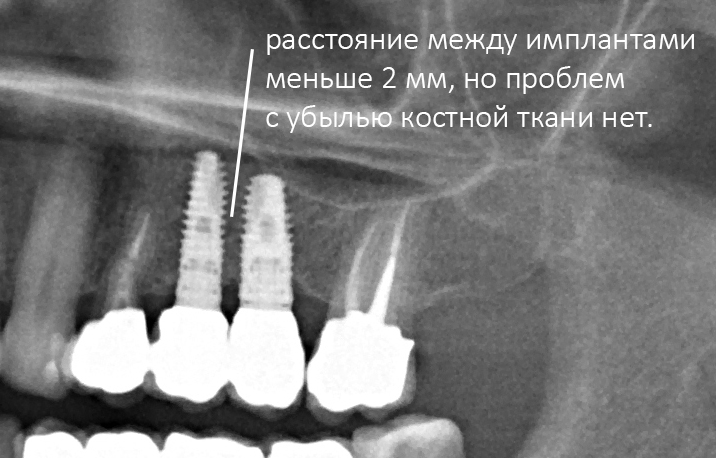

Рекомендации по установке имплантов. Для всех. Часть V.